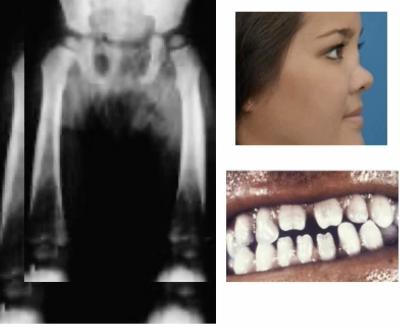

Treponema Pallidum - Gram negative spirochete which causes syphillis. Grown in special medium, slow, low oxygen conditions. Treated with penicillin. (Aortic aneurism and regurgitation)

Treponema Pallidum - Gram negative spirochete which causes syphillis. Grown in special medium, slow, low oxygen conditions. Treated with penicillin.

Treponema Pallidum - Gram negative spirochete which causes syphillis. Grown in special medium, slow, low oxygen conditions. Treated with penicillin